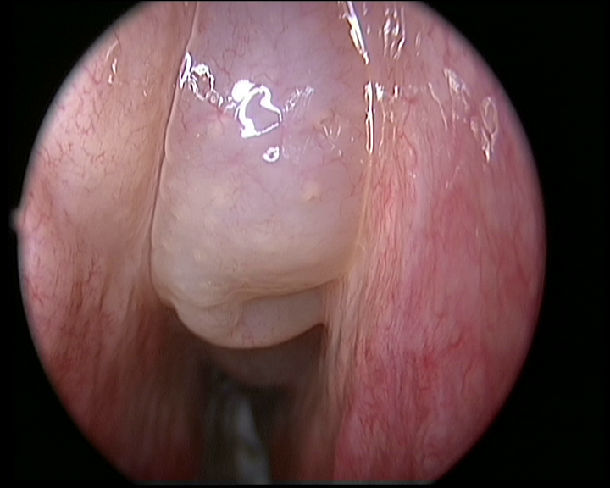

鼻息肉圖片

鼻息肉